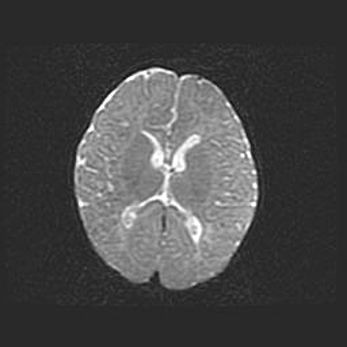

Сообщающаяся гидроцефалия. Кистозная энцефаломаляция головного мозга.

Возраст: 3 месяца 4 дня

Вес: 3100 г

Пол: женский

Окружность головы: 34 см

Срок гестации: 31 неделя

Кистозная энцефаломаляция головного мозга - одна из форм поражения головного мозга в детском возрасте. Характеризуется возникновением множественных и распространённых кист в коре, белом веществе и подкорковых образованиях головного мозга у плодов, новорождённых и детей раннего возраста. Развитие кистозной энцефаломаляции связано с внутриутробной асфиксией и гипотонией, родовой травмой, тромбозом синусов, пороками развития сосудов, инфекциями, сепсисом и другими причинами. Наиболее значимые инфекционные агенты: вирусы простого герпеса, цитомегалии, краснухи, токсоплазмы, энтеробактерии, золотистый стафилококк и другие.